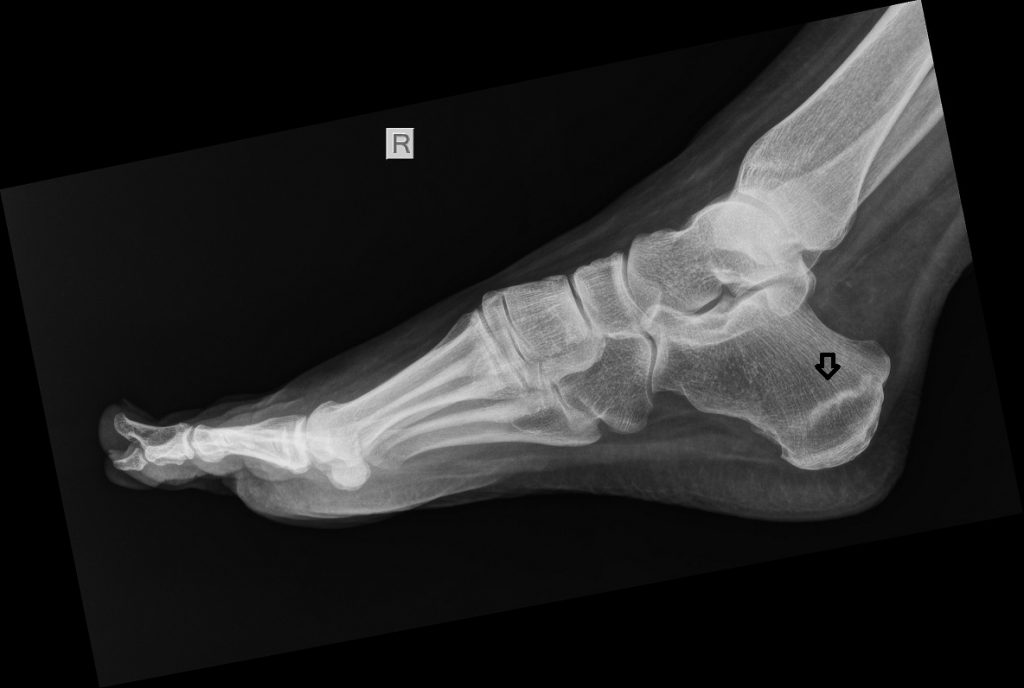

STRESS FRACTURE CALCANEUS

Heelpain in persons who stand long periods or walk far can be the result of a calcaneal stress fracture. Smoking or female sex seem to be risk factors to take into account. Treatment is a period of non weight bearing and vitamin D.